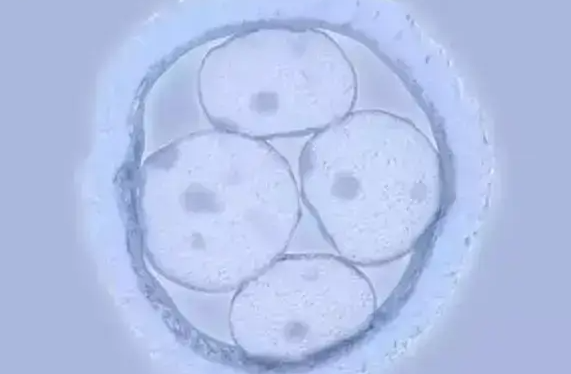

赴美前3-6个月需完成全面体检,女性重点监测AMH值评估卵巢储备,男性通过精液分析排查少精、弱精问题。若存在子宫内膜异位症、甲状腺疾病等基础病,需提前治疗至稳定状态。例如,子宫内膜厚度达8-12mm时移植,成功率较薄型子宫内膜提升35%。

促排卵阶段需按时注射FSH/HMG药物,并通过B超监测卵泡发育,医生会根据卵泡大小动态调整剂量。移植后48小时为“黄金着床期”,需严格卧床休息,避免弯腰、提重物等动作。保胎阶段需遵医嘱服用孕酮、雌激素药物,定期检测HCG翻倍情况,及时排查宫外孕等风险。